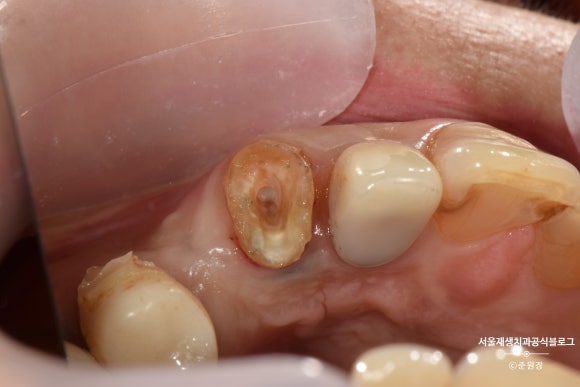

잇몸에 콕 박혀있던 요 녀석을

위 사진처럼 약~간 들어올린 상태로 고정시켰습니다.

치아가 살~짝 빠져있는 상태겠죠?

흔들리지 않겠냐고요?

약간의 생리적인 움직임만을 허용할 수 있는

레진-와이어 스플린팅을 시행합니다.

투명하고 낭창낭창한 플라스틱 와이어나 얇은 스텐와이어면 충분합니다.

인접치에 튼튼하게 고정되었습니다.

이 상태로 2주 기다려봅니다.